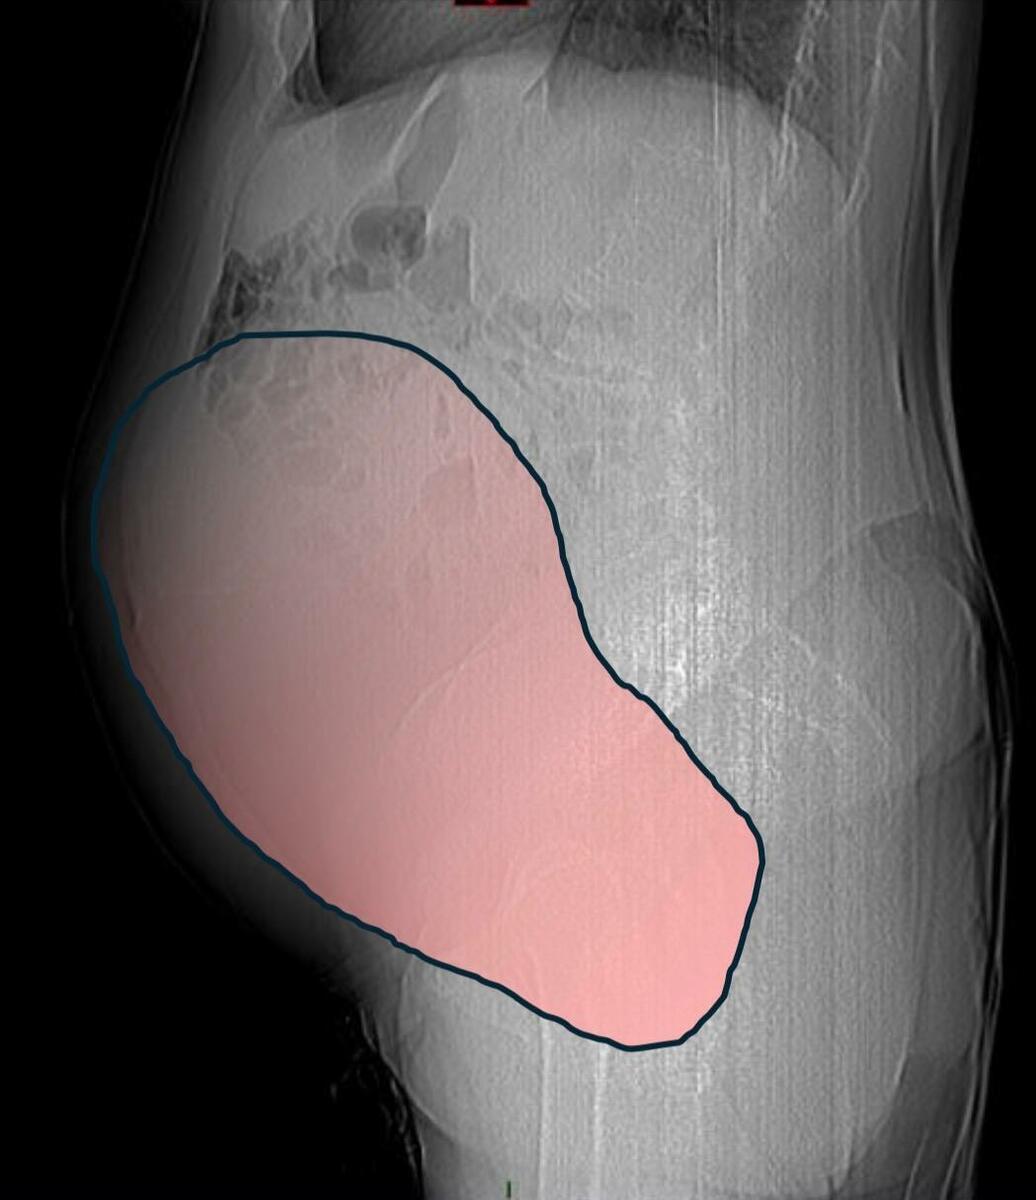

Per mesi la gigantesca cisti ovarica, con un diametro di circa 28 centimetri, è rimasta nascosta, senza dare segnali evidenti. La paziente non si era accorta di nulla. L’allarme è scattato quando la massa, associata alla presenza di una seconda neoplasia intestinale, ha iniziato a comprimere il colon, provocando sintomi acuti ed improvvisi fino ad una grave difficoltà intestinale non più ignorabile.

Fondamentale in questa fase il contributo della Radiologia dell'ospedale Sant’Anna, che fornisce l’imaging preoperatorio indispensabile per affrontare un quadro clinico di eccezionale complessità.

Durante l’intervento emerge tutta la gravità della situazione. La gigantesca neoplasia ovarica viene asportata: pesa circa 6 chilogrammi, con un volume paragonabile a quello di una gravidanza gemellare a termine. Ma non è l’unica minaccia. I sintomi più pericolosi sono legati alla sofferenza intestinale, che richiede un intervento immediato e coordinato di più specialisti.